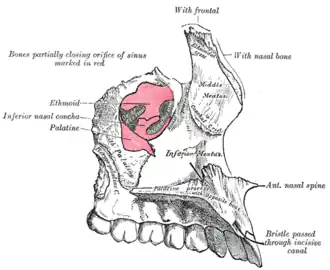

Position of palatine process (shown in red).

Position of palatine process (shown in red). -

Maxilla. Palatine process shown in red.

Maxilla. Palatine process shown in red. -

Roof, floor, and lateral wall of left nasal cavity.

Roof, floor, and lateral wall of left nasal cavity. -